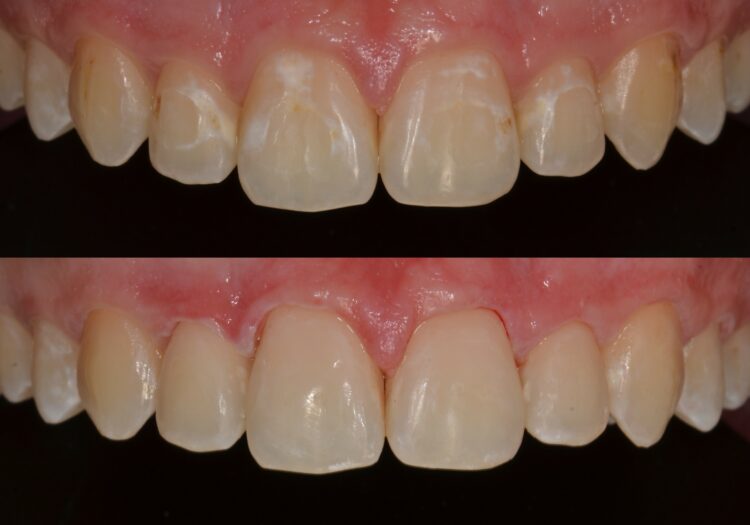

Estetické sanace

Přímé fasety z kompozitních materiálů, korekce tvaru zubů, cervikální defekty, plošné kazy po ortodontické léčbě.